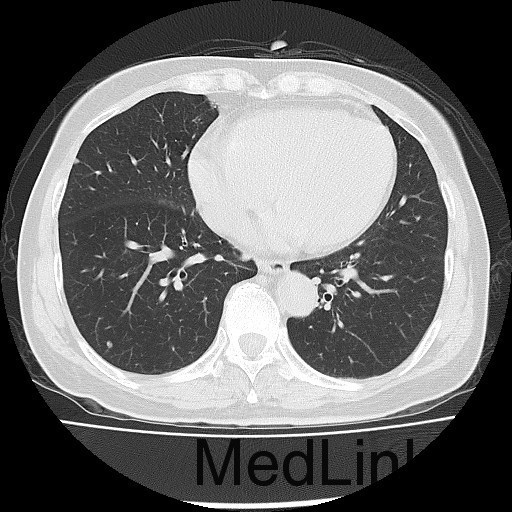

诊断:甲状腺恶性肿瘤(术后);手术后甲状腺功能减退。 治疗:入院时甲状腺球蛋白>455pmol/L,甲状腺素2.793uIU/ml,根据病情于2014-6-3予大剂量碘-131 100mCi清甲治疗;2014年6月全身碘扫示:全身多发异常摄碘组织,考虑甲状腺癌术后双侧甲状腺组织及锥状叶残留并全身多发骨转移。2014年9月胸部CT示:1、双肺多发转移瘤,并胸骨转移;胸1、8、10、腰1椎体内多发结节灶,考虑转移瘤可能性大。2、右肺中叶内侧段、双肺下叶散在慢性炎症。2014年12月全身碘扫:1.全身多处异常摄碘组织,考虑多发骨转移瘤。又于2014年12月复查甲状腺球蛋白抗体90.400U/mL,促甲状腺素6.914uIU/ml。遂于2014-12-22口服250mCi大剂量放射性碘-131。治疗后全身碘扫复查结果提示:2.左肺下叶摄碘组织,不排除转移瘤,建议进一步检查。与2014.6.6检查相比,颈部甲状腺部位放射性浓集灶消失,余病灶放射性浓集程度较前稍降低。

患者又于2015年10月胸部CT复查,结果提示:1、甲癌术后改变;双肺多发转移瘤,大部分病灶较前缩小,左肺下叶病灶较前增多,部分较前增大;胸骨转移;胸1、8、10、腰1椎体内多发结节灶,基本同前,考虑转移瘤可能性大。2、右肺中叶内侧段、左肺上叶舌段及双肺下叶散在慢性炎症。